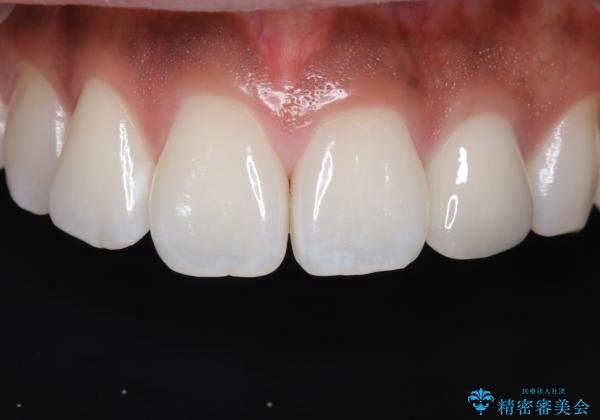

- 「前歯の歯の色が気になる」を主訴に来院された患者さんです。歯の大部分がプラスチックの材料で治療されていました。そこが劣化し変色していたためオールセラミッククラウンで治療を行いました。前歯の色を全体的に白くするために当院でオフィスホワイトニングも行いました。

- 15万4千円(オールセラミッククラウンスペシャル14万3千円+仮歯1万1千円)費用は治療当時の料金となります

左上2番の大部分がプラスチックの材料で治療されていました。そのプラスチックの材料が劣化して変色し虫歯になっている状態でした。なので古いプラスチックの材料を全て除去し、その下の虫歯を取った後、オールセラミッククラウンで治療を行いました。オールセラミッククラウンを装着する前に当院にてホワイトニングを行いました。